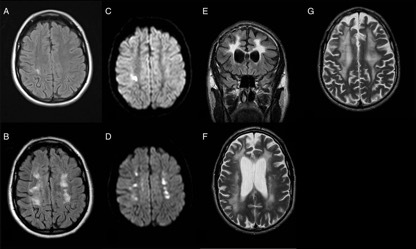

案例 10:2 例患者,诊断为 HDLS。

图 11 第一例患者 34 岁时的 MRI 提示右顶叶 FLAIR[A] 高信号和 DWI[C] 弥散受限;36 岁的 MRI 提示 FLAIR[B] 和 DWI[D] 上病灶进展;第二例患者 48 岁时的 MRI 提示 FLAIR[E] 和 T2WI[F~G] 上广泛的白质高信号